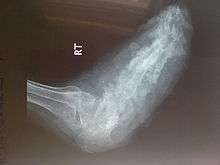

Radiographs (originally called roentgenographs, named after the discoverer of X-rays, Wilhelm Conrad Röntgen) are produced by transmitting X-rays through a patient. The X-rays are projected through the body onto a detector; an image is formed based on which rays pass through (and are detected) versus those that are absorbed or scattered in the patient (and thus are not detected). Röntgen discovered X-rays on November 8, 1895 and received the first Nobel Prize in Physics for their discovery in 1901.

In film-screen radiography, an X-ray tube generates a beam of X-rays, which is aimed at the patient. The X-rays that pass through the patient are filtered through a device called an grid or X-ray filter, to reduce scatter, and strike an undeveloped film, which is held tightly to a screen of light-emitting phosphors in a light-tight cassette. The film is then developed chemically and an image appears on the film. Film-screen radiography is being replaced by computed radiography (CR) but more recently by digital radiography (DR) and the EOS imaging.[1] In the two latest systems, the X-rays strike sensors that converts the signals generated into digital information, which is transmitted and converted into an image displayed on a computer screen. In digital radiography the sensors shape a plate, but in the EOS system, which is a slot-scanning system, a linear sensor vertically scans the patient.

Plain radiography was the only imaging modality available during the first 50 years of radiology. Due to its availability, speed, and lower costs compared to other modalities, radiography is often the first-line test of choice in radiologic diagnosis. Also despite the large amount of data in CT scans, MR scans and other digital-based imaging, there are many disease entities in which the classic diagnosis is obtained by plain radiographs. Examples include various types of arthritis and pneumonia, bone tumors (especially benign bone tumors), fractures, congenital skeletal anomalies, etc.